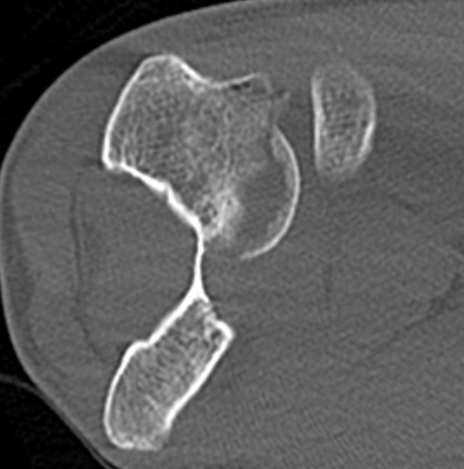

Dubberly Classification

| Type I | Type Ii | Type III |

|

Capitellar fracture

Capitellum + trochlea fracture In one piece Double arc sign seen on xray |

Capitellum + trochlea fractures In two separate pieces |